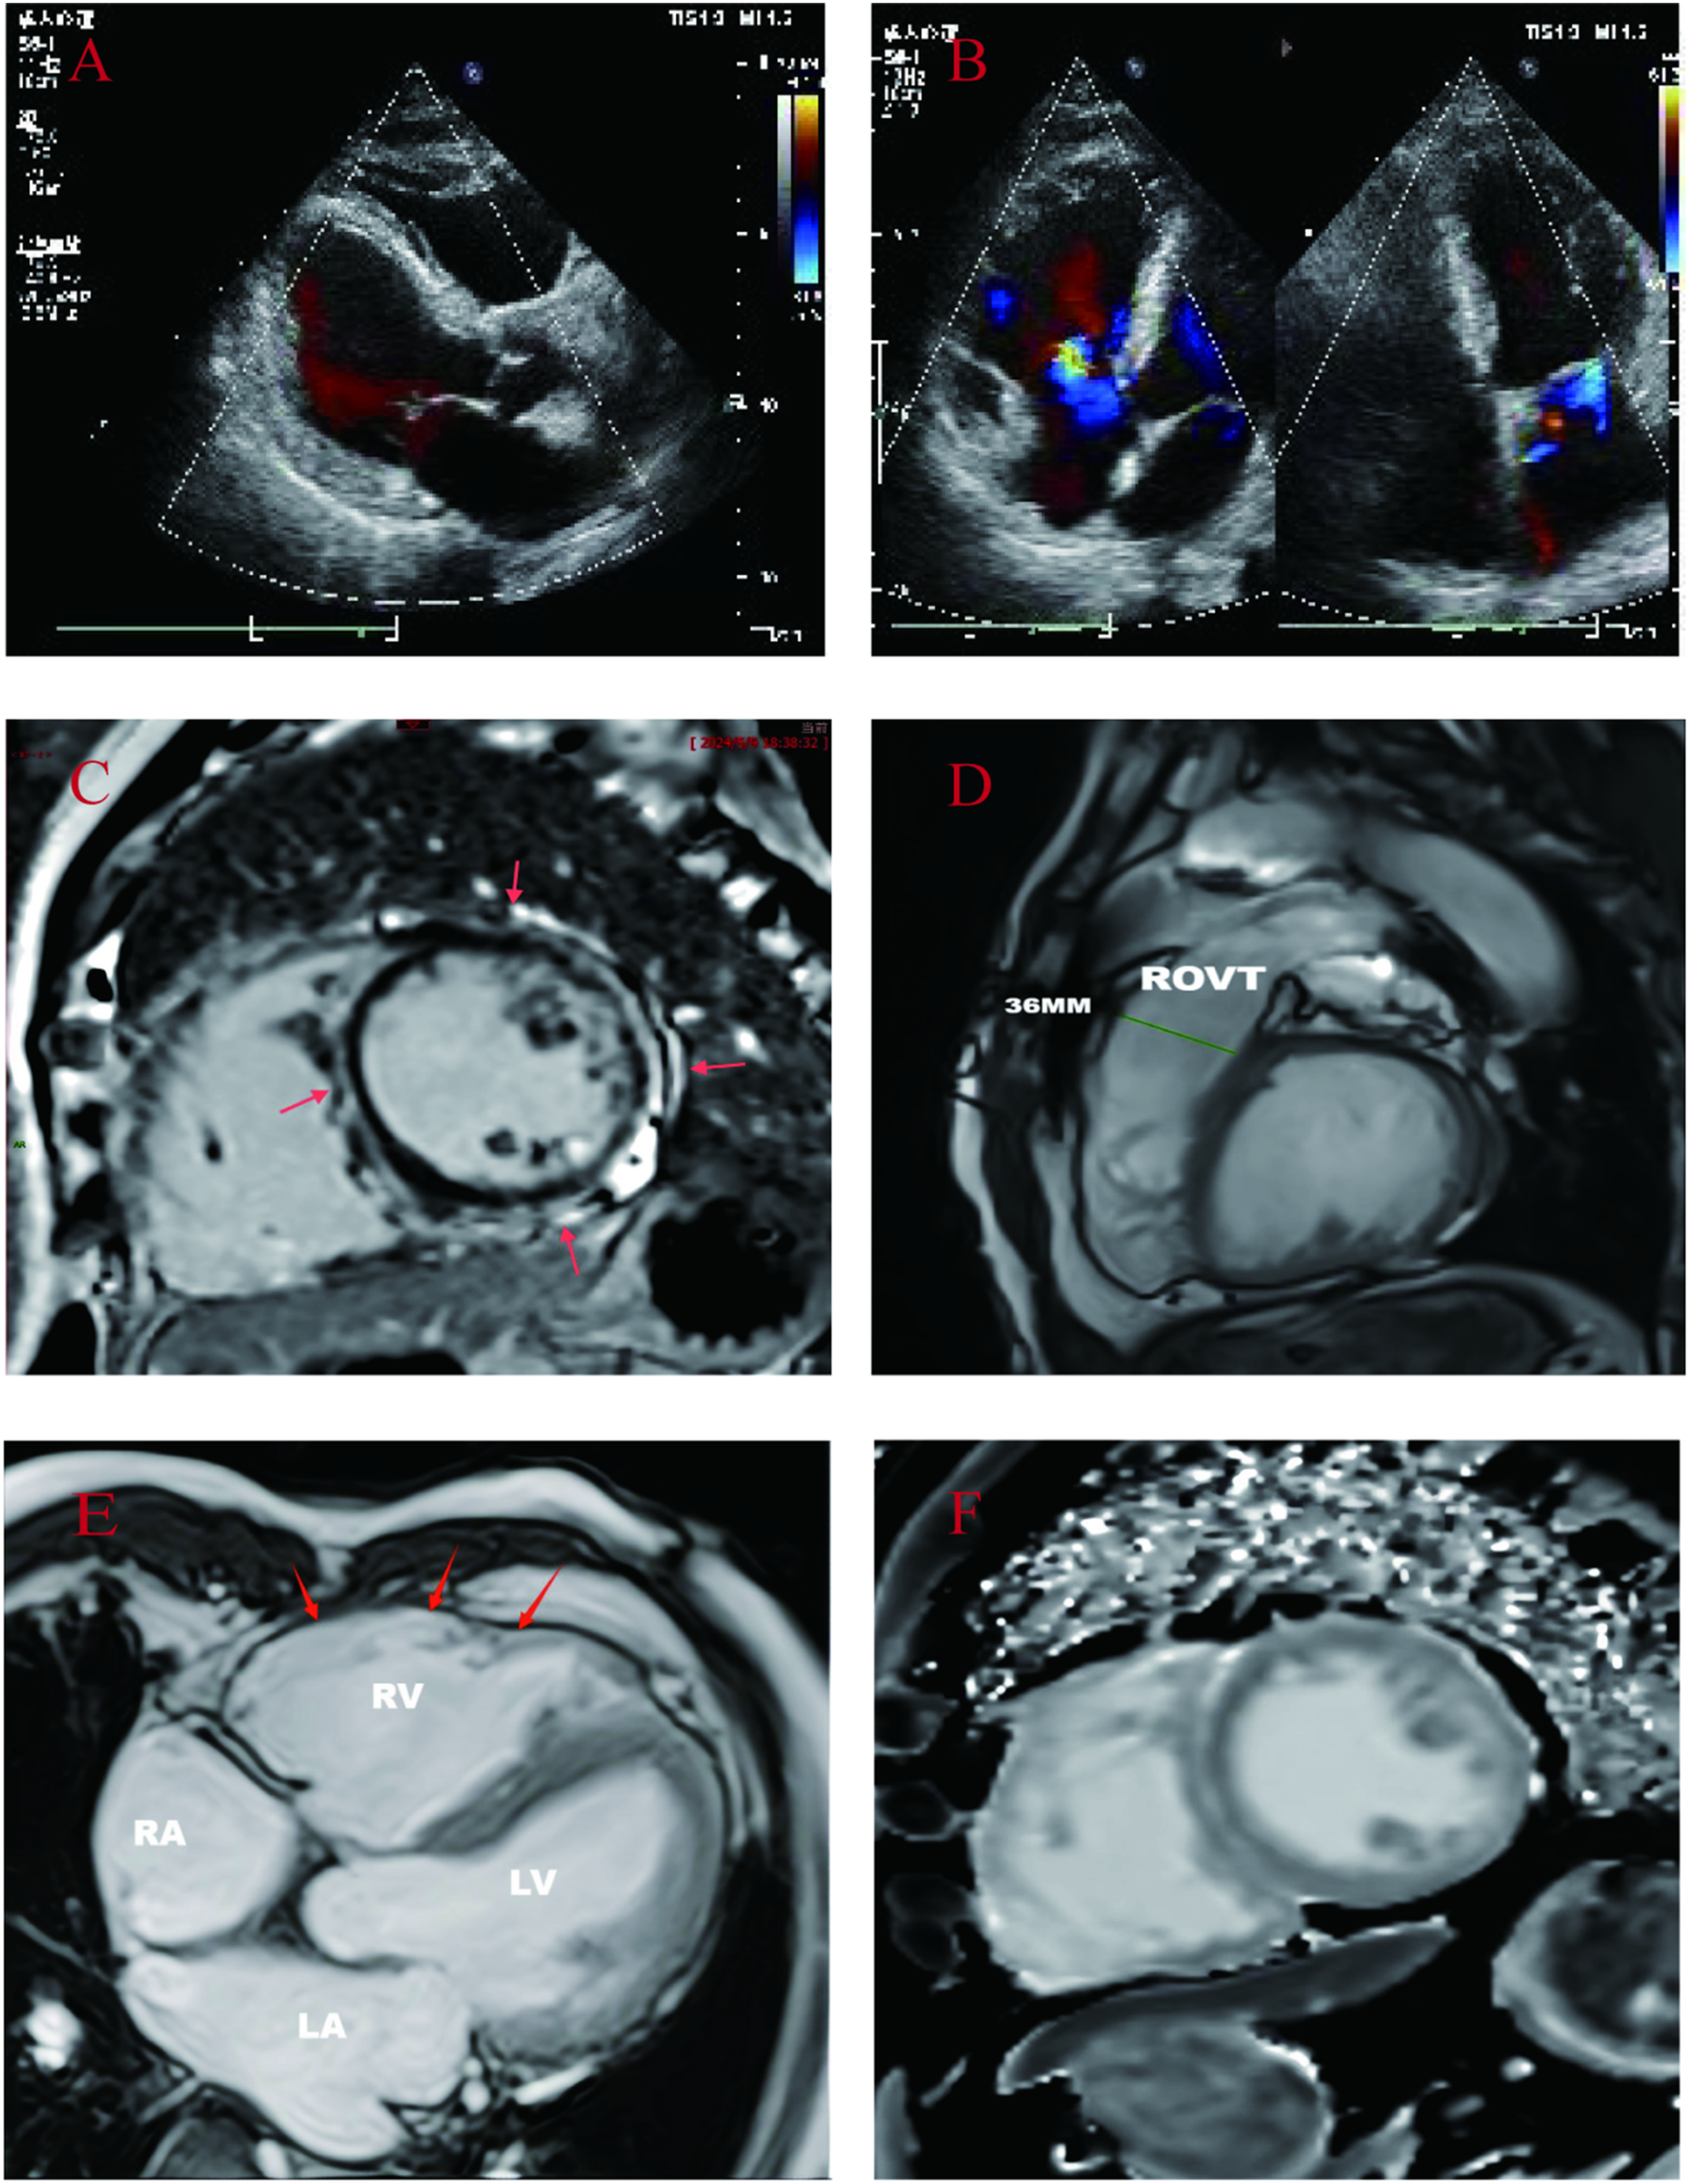

A 71-year-old male patient (proband) presented to the hospital with recurrent sudden syncope, and comprehensive evaluation revealed that his electrocardiogram revealed a prolonged Q-T interval, low-voltage QRS complexes in the limb leads, and multiple episodes of nonsustained ventricular tachycardia (QRS complexes with left bundle branch block morphology) (Figures 1A–C); echocardiography and magnetic resonance imaging revealed global enlargement of the left and right ventricles, global hypokinesia, multiple thinning of the ventricular wall, ventricular aneurysm in the right ventricle (regional myocardial paradoxical movement), widening of the right ventricular outflow tract, and decreased left and right ventricular ejection fractions (Figures 2A,B,D,E); magnetic resonance enhancement (LGE) revealed subepicardial free walls in the middle left ventricle, interventricular septal wall, and transmural myocardial fibrosis images in the right ventricular inferior wall (Figures 2C,F) (Supplementary Material S1), and coronary angiography revealed plaque formation in the proximal left anterior descending artery, 30% stenosis, and no significant stenosis in the remaining vessels. In view of the proband's clinical manifestations and multimodality imaging results, we suspected that he had ACM and performed whole exome sequencing (WES): DNA was first extracted from peripheral blood, libraries were constructed using Agilent SureSelectXT V6, and sequenced on the Illumina NovaSeq 6,000 platform.Data analysis was screened by BWA alignment (GRCh37/hg19), PICARD de-duplication, SnpEff and ANNOVAR annotation, focusing on exonic regions and non-coding variants affecting splicing (Splice-AI > 0.2), combined with disease database and Shengxin software prediction. The pathogenicity of genetic variants was judged according to the American College of Medical Genetics and Genomics (ACMG) and Association for Molecular Pathology (AMP) criteria (9), the results revealed that he carried three rare mutations: the heterozygous missense variant c.1786G > A (p.Asp596Asn) in the LMNA gene(suspected causative), the heterozygous variant c.8187delC (p.Gln2730SerfsTer16) in the DSP gene(suspected causative), and the heterozygous missense variant c.5351A > G (p.His1784Arg) in the AKAP9 gene (unknown significance) (Figure 1D). All variants were verified by Sanger sequencing, and co-segregation analysis was performed on family members. The proband was diagnosed with arrhythmogenic biventricular cardiomyopathy and Q-T interval prolongation according to the revised 2020 ITF diagnostic criteria for ACM and was considered to have a high risk of malignant arrhythmia and sudden death. Radiofrequency ablation and drug therapy were performed after consultation with the proband and his family members, considering the hereditary nature of the disease, we conducted genetic testing and comprehensive evaluations for the proband's family members.

Figure 2

(A,B): Proband's echocardiogram: showed whole heart enlargement, overall movement weakened, left ventricular EF45% FS23%. (C–F): CMR images of probands. (C): Cardiac short-axis LGE: delayed enhancement between the free wall of the middle left ventricle and the subepicardium of the right ventricle, and delayed enhancement between the muscular walls of the interventricular septum. (D): Right ventricular outflow tract widening: 36 mm. (E): Left and right ventricular wall multiple thinning, right ventricular wall tumor (local myocardial contradictory movement). (F): Short axis native T1: increased T1 value between subepicardial left ventricular free wall and interventricular septum muscle wall.